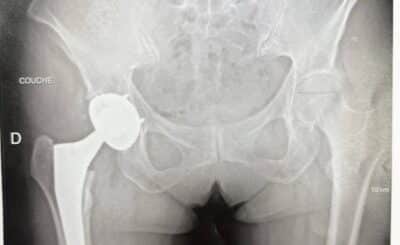

Implanting a hip prosthesis in coxopathy with normal radiographs

The most common procedure in hip surgery is primary total hip replacement for advanced hip osteoarthritis. In typical ca...